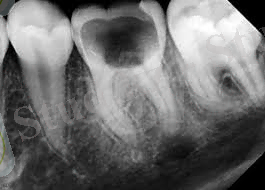

Тіс жегінің рентгендік көрінісі.

Тісжегінің кіреукедегі дақты кезеңінденегізі сыртқы бетке қараған, ал ұшы кіреуке-дентин шекарасына бағытталған үшбұрышты тәріздес зақымдану ошағы анықталады. поляризациялы микроскопиялау әдісімен зерттегенде кіреукеде үшбұрыш пішінді жарақат ошағы анықталады және оның табаны кіреукенің сырт бетіне қарай орналасқан . Жарақат ошағындағы өзгерістер дақтың аумағымен тығыз байланысты. Егер дақтың көлемі 2-мм аспаса, шлифте мөлдір және қараңғы белдеулер анықталады. Тісжегі дағының көлемі ұлғайған кезде үш белдеуді (зоны) ажыратады - жарақат денесі (тело поражения), қараңғы және мөлдір белдеулер.

3. Ортаңғы тісжегі - жарақат кіреукеден дентинге ауысады және оның жабынды қабатында орналасады. Даму ерекшелігіне қарай клиникалық белгілері дамиды. Егер жедел даму болса температуралық, химиялық, механикалық әсерден ауырады. Баяу дамыса ешқандай ауыру сезімі болмайды. Науқастың негізгі шағымы: тісте белгілі бір ойықтың пайда болғанын айтады. Көріп тексергенде тісте орта тереңдікте (2-3 мм) қуыс анықталады. Жедел дамығанда қабырғасында жұмсарған ақ дентин көп, тез алынады. Баяу дамығанда дентин сарғыш -қоңыр, қоңыр түсті, қаттылау болады. Шұқып тексергенде ауыру сезімі дентин-эмаль шекарасында пайда болады. Түбі ауырмайды. Қосалқы әдіспен электр қозғыштығын ЭОД тексеру керек. Бұнда өзгермеген 2-6 мкА. Қорытынды диагноз қою үшін терең кариестен және периодонттың созылмалы қабынуынан, сына тәрізді ақаудан ажырата білу керек. Терең тісжегіден ажырату үшін тереңдігін анықтаймыз. Ал периодонттың созылмалы қабынуын ажырату үшін рентгенография мен ЭОД арқылы тексеріледі. Периодонтқа ЭОД төмен 200 мкА болуы керек. Рентген суретінде белгілі өзгерістер болады: периодонт саңылауы кеңейген, түбір ұшында қара көлеңке және сүйек тіндерінің сорылу белгілері.